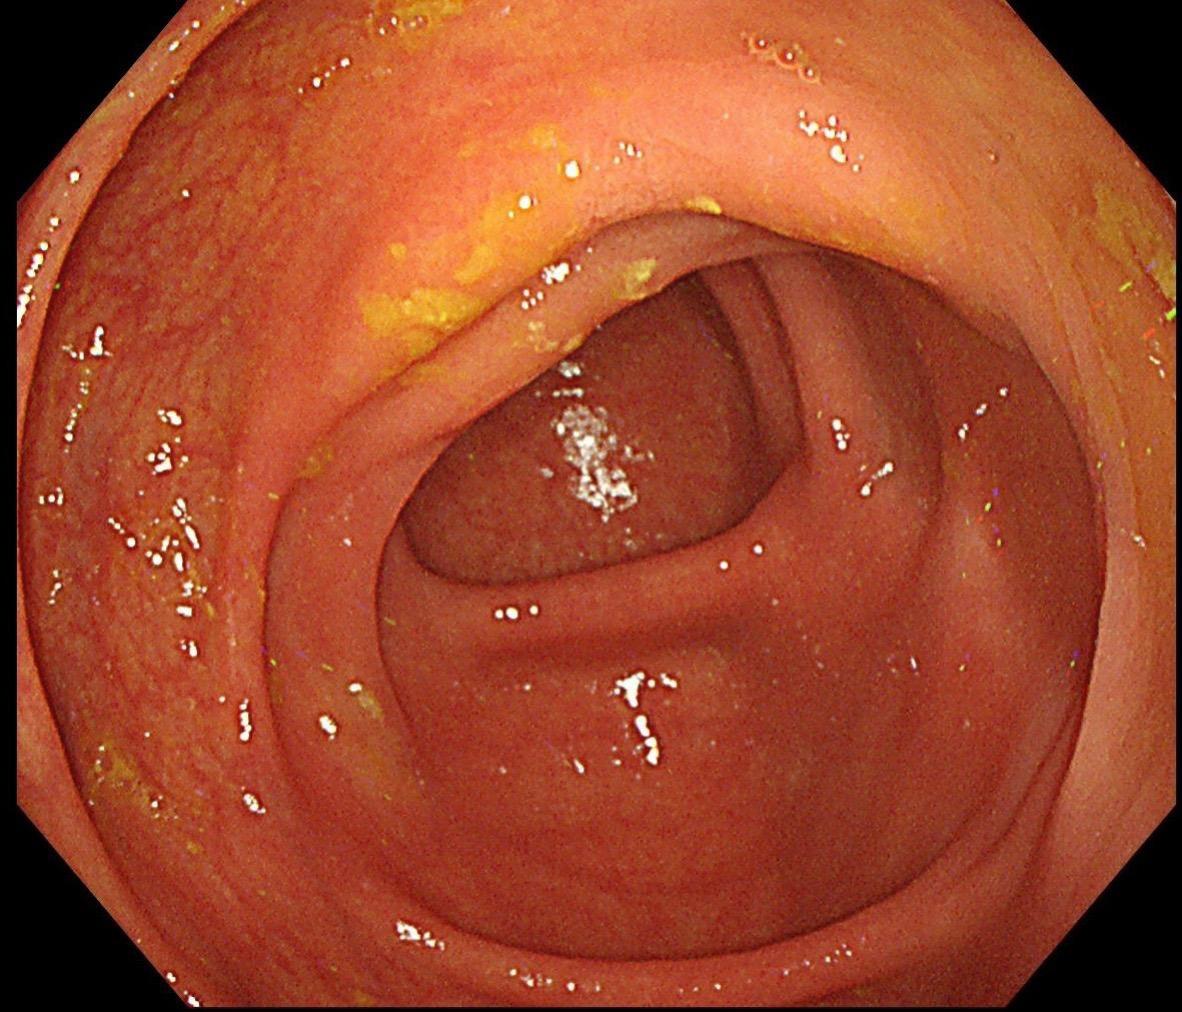

小小的糜烂一枚。这样的病灶,就算结果是阴性的,也很有意义~

哇哦,树莓哎。小凹上皮肿瘤伴高级别上皮内瘤变,日常工作中并不常见,可惜...